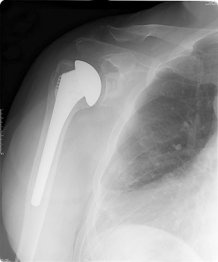

Shoulder implant

Shoulder replacements benefit most patients for more than ten years, study shows

More than 90 per cent of shoulder replacement implants last more than ten years, according to the largest study of its kind.

The study found that at ten years, more than 90 per cent of shoulder replacements were still working well, and that patients continued to report that the operation had benefitted them.